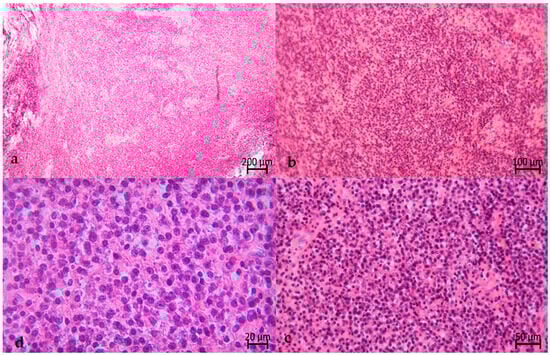

2. The Case